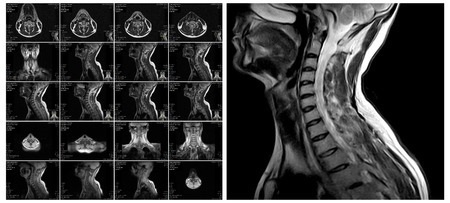

レントゲン検査では骨の変形具合を確認します。

神経の通り道である脊柱管の前後を見たり、首を前後に傾けた状態で不安定さがないかなどを確認します。

MRI検査ではレントゲン検査では確認できない椎間板や脊髄の状態を確認します。椎間板変性の程度、神経圧迫の評価が可能になります。